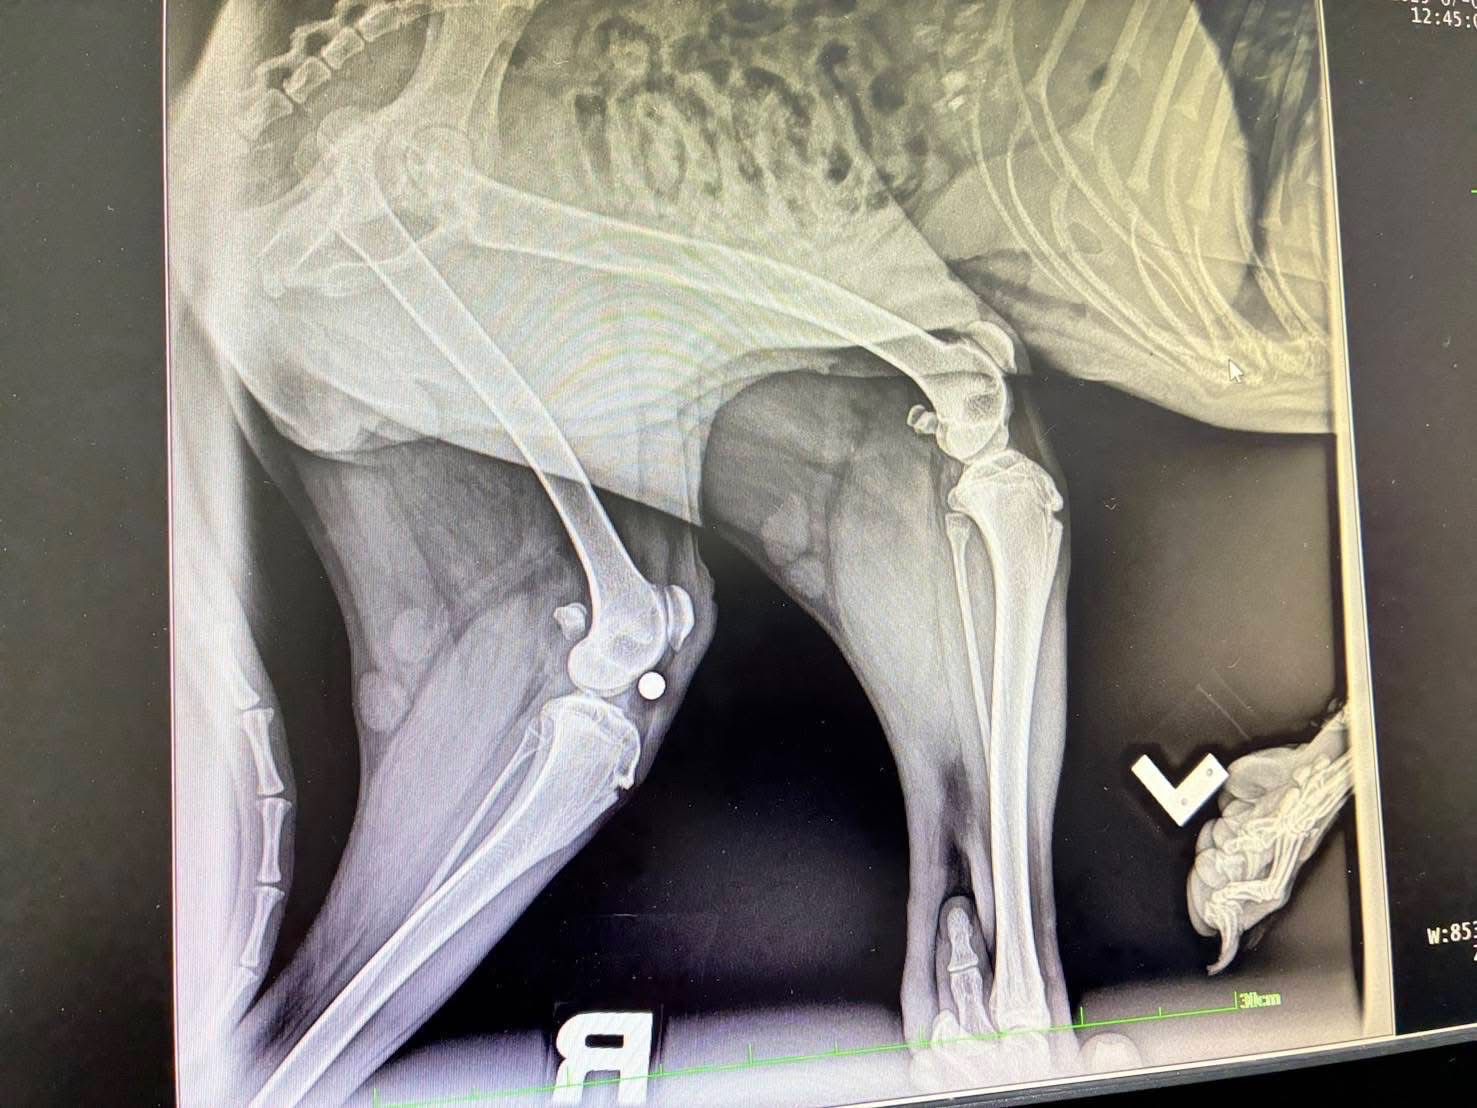

เมื่อวันที่ 1 กรกฎาคม 2568 พระครูสังฆรักษ์วีรวัฒน์ วีรวฑฺฒโน (พระครูอ๊อด) วัดเจดีย์หลวงวรวิหาร จังหวัดเชียงใหม่ เปิดเผยว่า ได้รับรายงานจากมูลนิธิ ดิอาร์ค ในพระราชูปถัมภ์ ซึ่งรับดูแลสุนัขพันธุ์ร็อตไวเลอร์จำนวน 4 ตัวที่ถูกนำไปทิ้งไว้กลางป่าในสภาพหิวโซและมีอาการบาดเจ็บหลายแห่ง โดยหนึ่งในสี่ตัวนั้นอยู่ในอาการบาดเจ็บสาหัส ล่าสุดเจ้าหน้าที่เไดมูลนิธิฯได้ทำการตรวจพบโลหะคล้ายกระสุนฝังอยู่ในร่างกายและอยู่ระหว่างดำเนินการผ่าตัดนำออกอย่างเร่งด่วน